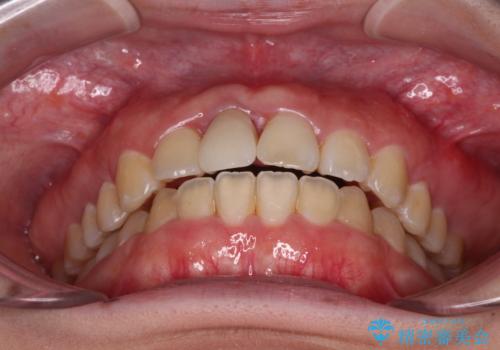

- 中学生の頃にぶつけた前歯に不格好なクラウンが装着されており、出っ歯な印象になっていることを気にして来院された患者様です。

ぶつけてしまった歯は保存が困難な状況であったので抜歯をし、ワイヤー矯正により歯列を整えつつ前歯の突出感を解消することとしました。

矯正治療後にはインプラント補綴治療を行うこととしました。